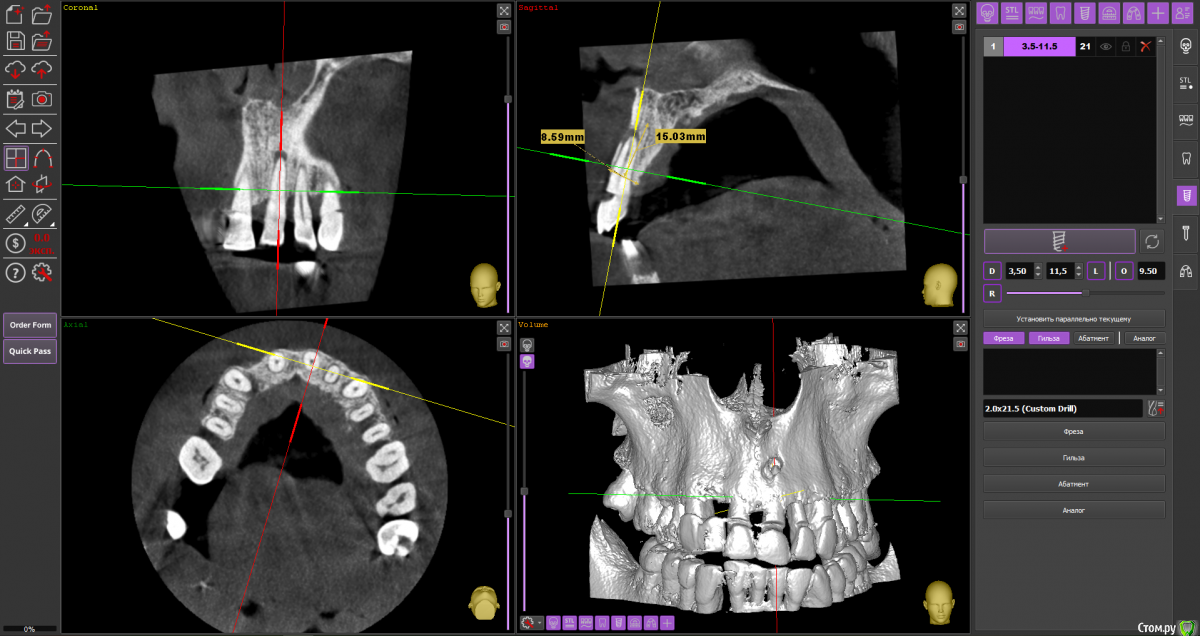

almaz7888 Опубликовано 28 января, 2021 Поделиться Опубликовано 28 января, 2021 Доброе утро коллеги! Планирую одномоментную имплантацию в область 2.1 зуба ( AnyRidge 3.5*11.5). В области апекса костный дефект. Думаю заполнить ксенографтом и перекрыть резорбируемой мембраной 1.5*2.0. Думал насчет спейсера Стоит ли такой имплант сразу нагрузить? или же лучше сделать адгезивный мост. Ссылка на комментарий

alboard Опубликовано 28 января, 2021 Поделиться Опубликовано 28 января, 2021 В том положении, которое на кт, сомневаюсь, что получите торк и сможете нагрузить... Взять подлиннее, поставить небнее и заглубить еще 4 Ссылка на комментарий

Irouil Опубликовано 28 января, 2021 Поделиться Опубликовано 28 января, 2021 Винт длиннее, выход в резцовый, стт, временная коронка 1 Ссылка на комментарий

almaz7888 Опубликовано 28 января, 2021 Автор Поделиться Опубликовано 28 января, 2021 Спасибо, тогда возьму 3.5*15. А резцовый нерв коагулирую и заполняю канал графтом или же можно без прижигания обойтись? Ссылка на комментарий

Astronaft Опубликовано 29 января, 2021 Поделиться Опубликовано 29 января, 2021 Я в похожей ситуации взял 4.5мм диаметр, БиоОсс и СТ трансплантат.AnyRidge тот который имеет сердцевину 3.5мм и глубокую агрессивную резьбу - очень хорошо врезается, риск лизиса кости меньше за счет места между витками. 2 Ссылка на комментарий